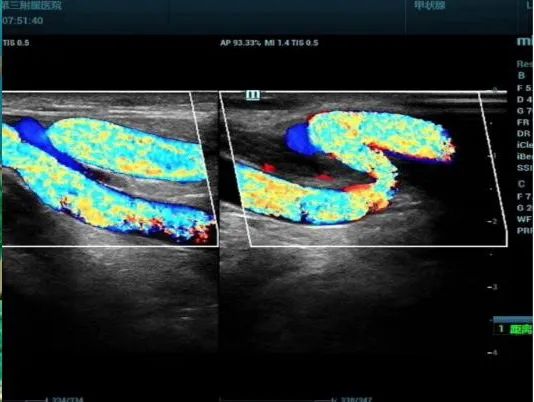

3.血液透析动静脉造瘘术前和术后的血管评估及配合临床行超声引导下内瘘血管球囊扩张术:术前超声可对动、静脉血管的管径、管壁情况、管腔通畅与否、走行状况、有无畸形变异及位置、有无侧支及其位置、血管扩张能力、对动静脉距离给临床诊疗提供依据。术后可对造瘘血管及瘘口有无狭窄、有无血栓形成及血管闭塞、有无窃血综合征、有无静脉瘤样扩张进行评估,以便给临床提供进一步的诊疗依据。